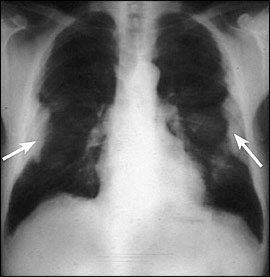

figure2

胸膜プラークを発達させ、前にアスベストの著しい肺実質の再構築と組織破壊(蜂窩肺)

曝露経験のある患者の胸部X線。

B良性胸膜疾患 benign pleural disease

アスベスト吸入において最も一般的な病理学的肺反応は、胸膜プラークの発達である(figure2)。時間と共に、コラーゲンは胸膜で沈殿して、固まるかもしれない。大部分のプラークは完全に症状がない。そしてプラークが悪性病巣に変わる証拠がない。プラークはアスベストへの深刻で長い期間による曝露によって、おおよそ50%の人に起こるため、アスベスト曝露の目印となる。健康診断時などの胸部X線検査で気づかれることが多い。中には、胸膜肥厚部分に隣接した末梢肺が部分的に虚脱を起こし、胸部X線写真上、円形の腫瘤様陰影を呈することがあり、これを円形無気肺または円形無気性偽腫瘍と呼んでいる。これらの3つの胸膜疾患は職業上アスベスト暴露を受けた場合に生じる疾患である。